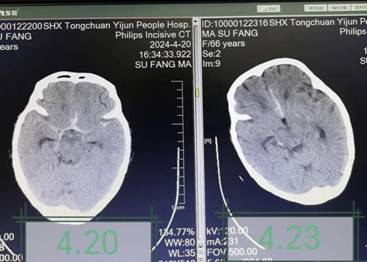

治疗前后颅脑CT对比,颅脑水肿及出血减轻